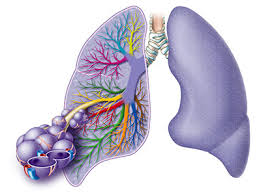

In den zu großen Blasen staut sich die Atemluft und die Ausatmung ist behindert. Der Auftritt eines Lungenemphysems geht einher mit der unumkehrbaren Schädigung der kleinsten Luftbläschen in der Lunge den sogenannten Alveolen. Beschwerden können sich mit leichten Brustschmerzen zeigen oder im schlimmsten Fall mit einem Kreislaufstillstand.

Charakteristisches Symptom bei einem Lungenemphysem ist die Atemnot besonders unter Belastung. Pneumothorax tritt auf wenn Luft in den Raum zwischen der Brustwand und der Lunge eintritt der als Pleuraspalt bezeichnet wird. Daher bei Atemnot und stechenden Schmerzen im Lungenbereich sofort die Rettung rufen.

Atemnot zuerst nur bei körperlicher Anstrengung später auch in Ruhe Husten verminderte Leistungsfähigkeit erhöhte Infektanfälligkeit. Befindet sich Flüssigkeit oder Sekret in der Lunge so wird der Körper als Schutzmechanismus versuchen dieses.